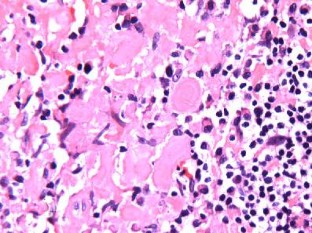

The endoscopic biopsy demonstrated that the mass was amyloid in nature. An extensive systemic workup revealed an absence of inflammatory process, systemic amyloidosis, or plasma cell dyscrasia. The patient was treated with a combination of surgery and radiotherapy, showing no evidence of recurrence or progression at his 1‑year follow-up.